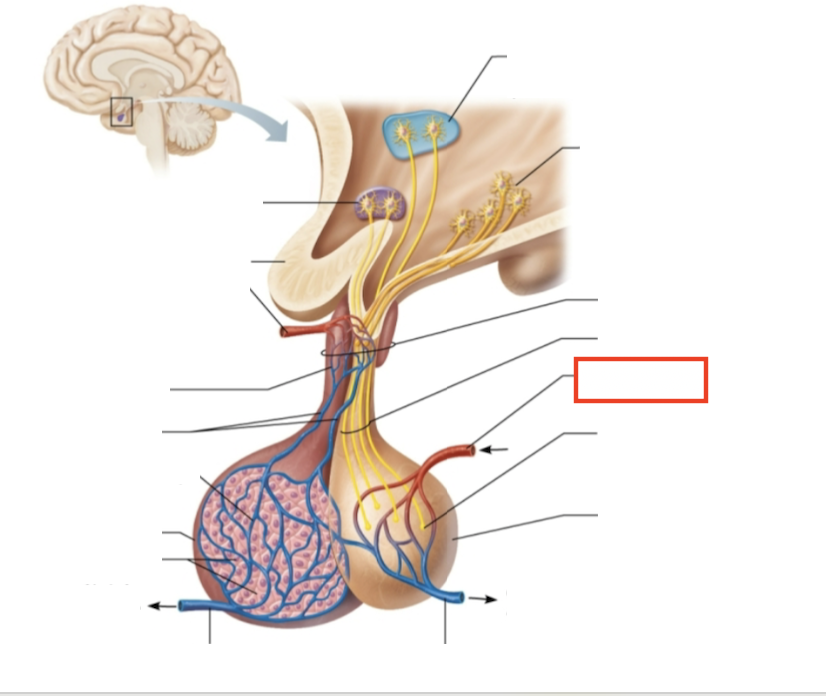

What structure is highlighted?

hypothalamic neurons in the paraventricular nuclei

What structure is highlighted?

neurons in the ventral hypothalamus

What structure is highlighted?

infundibulum (connecting stalk)

What structure is highlighted?

hypothalamic-hypophyseal tract

What structure is highlighted?

inferior hypophyseal artery

What structure is highlighted?

neurohypophysis (storage area for hypothalamic hormones)

What structure is highlighted?

posterior pituitary

What molecules are produced here?

oxytocin, ADH

What structure is highlighted?

venule

What structure is highlighted?

venule

What molecules are produced here?

TSH, FSH, LH, ACTH, GH, PRL

What structure is highlighted?

secretory cells of adenohypophysis

What structure is highlighted?

anterior pituitary

What structure is highlighted?

secondary capillary plexus

What structure is highlighted?

hypophyseal portal veins

What structure is highlighted?

primary capillary plexus

What structure is highlighted?

superior hypophyseal artery

What structure is highlighted?

superior hypophyseal artery

What structure is highlighted?

optic chiasma

What structure is highlighted?

hypothalamic neurons in the supraoptic nuclei